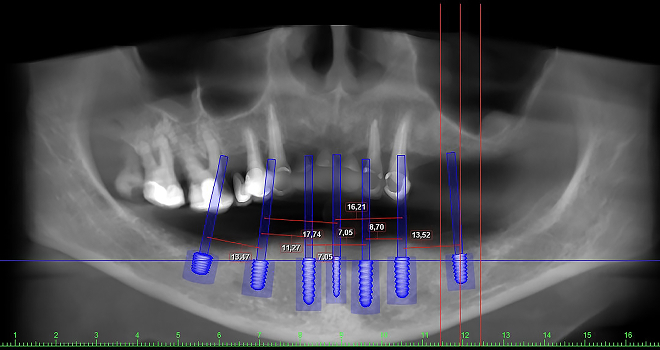

트리오스5 스캐너와 전용 디자인 프로그램 (임플란트 스튜디오),

3D 프린터를 통해 정밀한 진단과 개인 맞춤 치료 계획을 수립합니다.

최신식 디지털 기술을 바탕으로 환자 한 분 한 분에게 최적화된 진료를 제공해 드립니다.